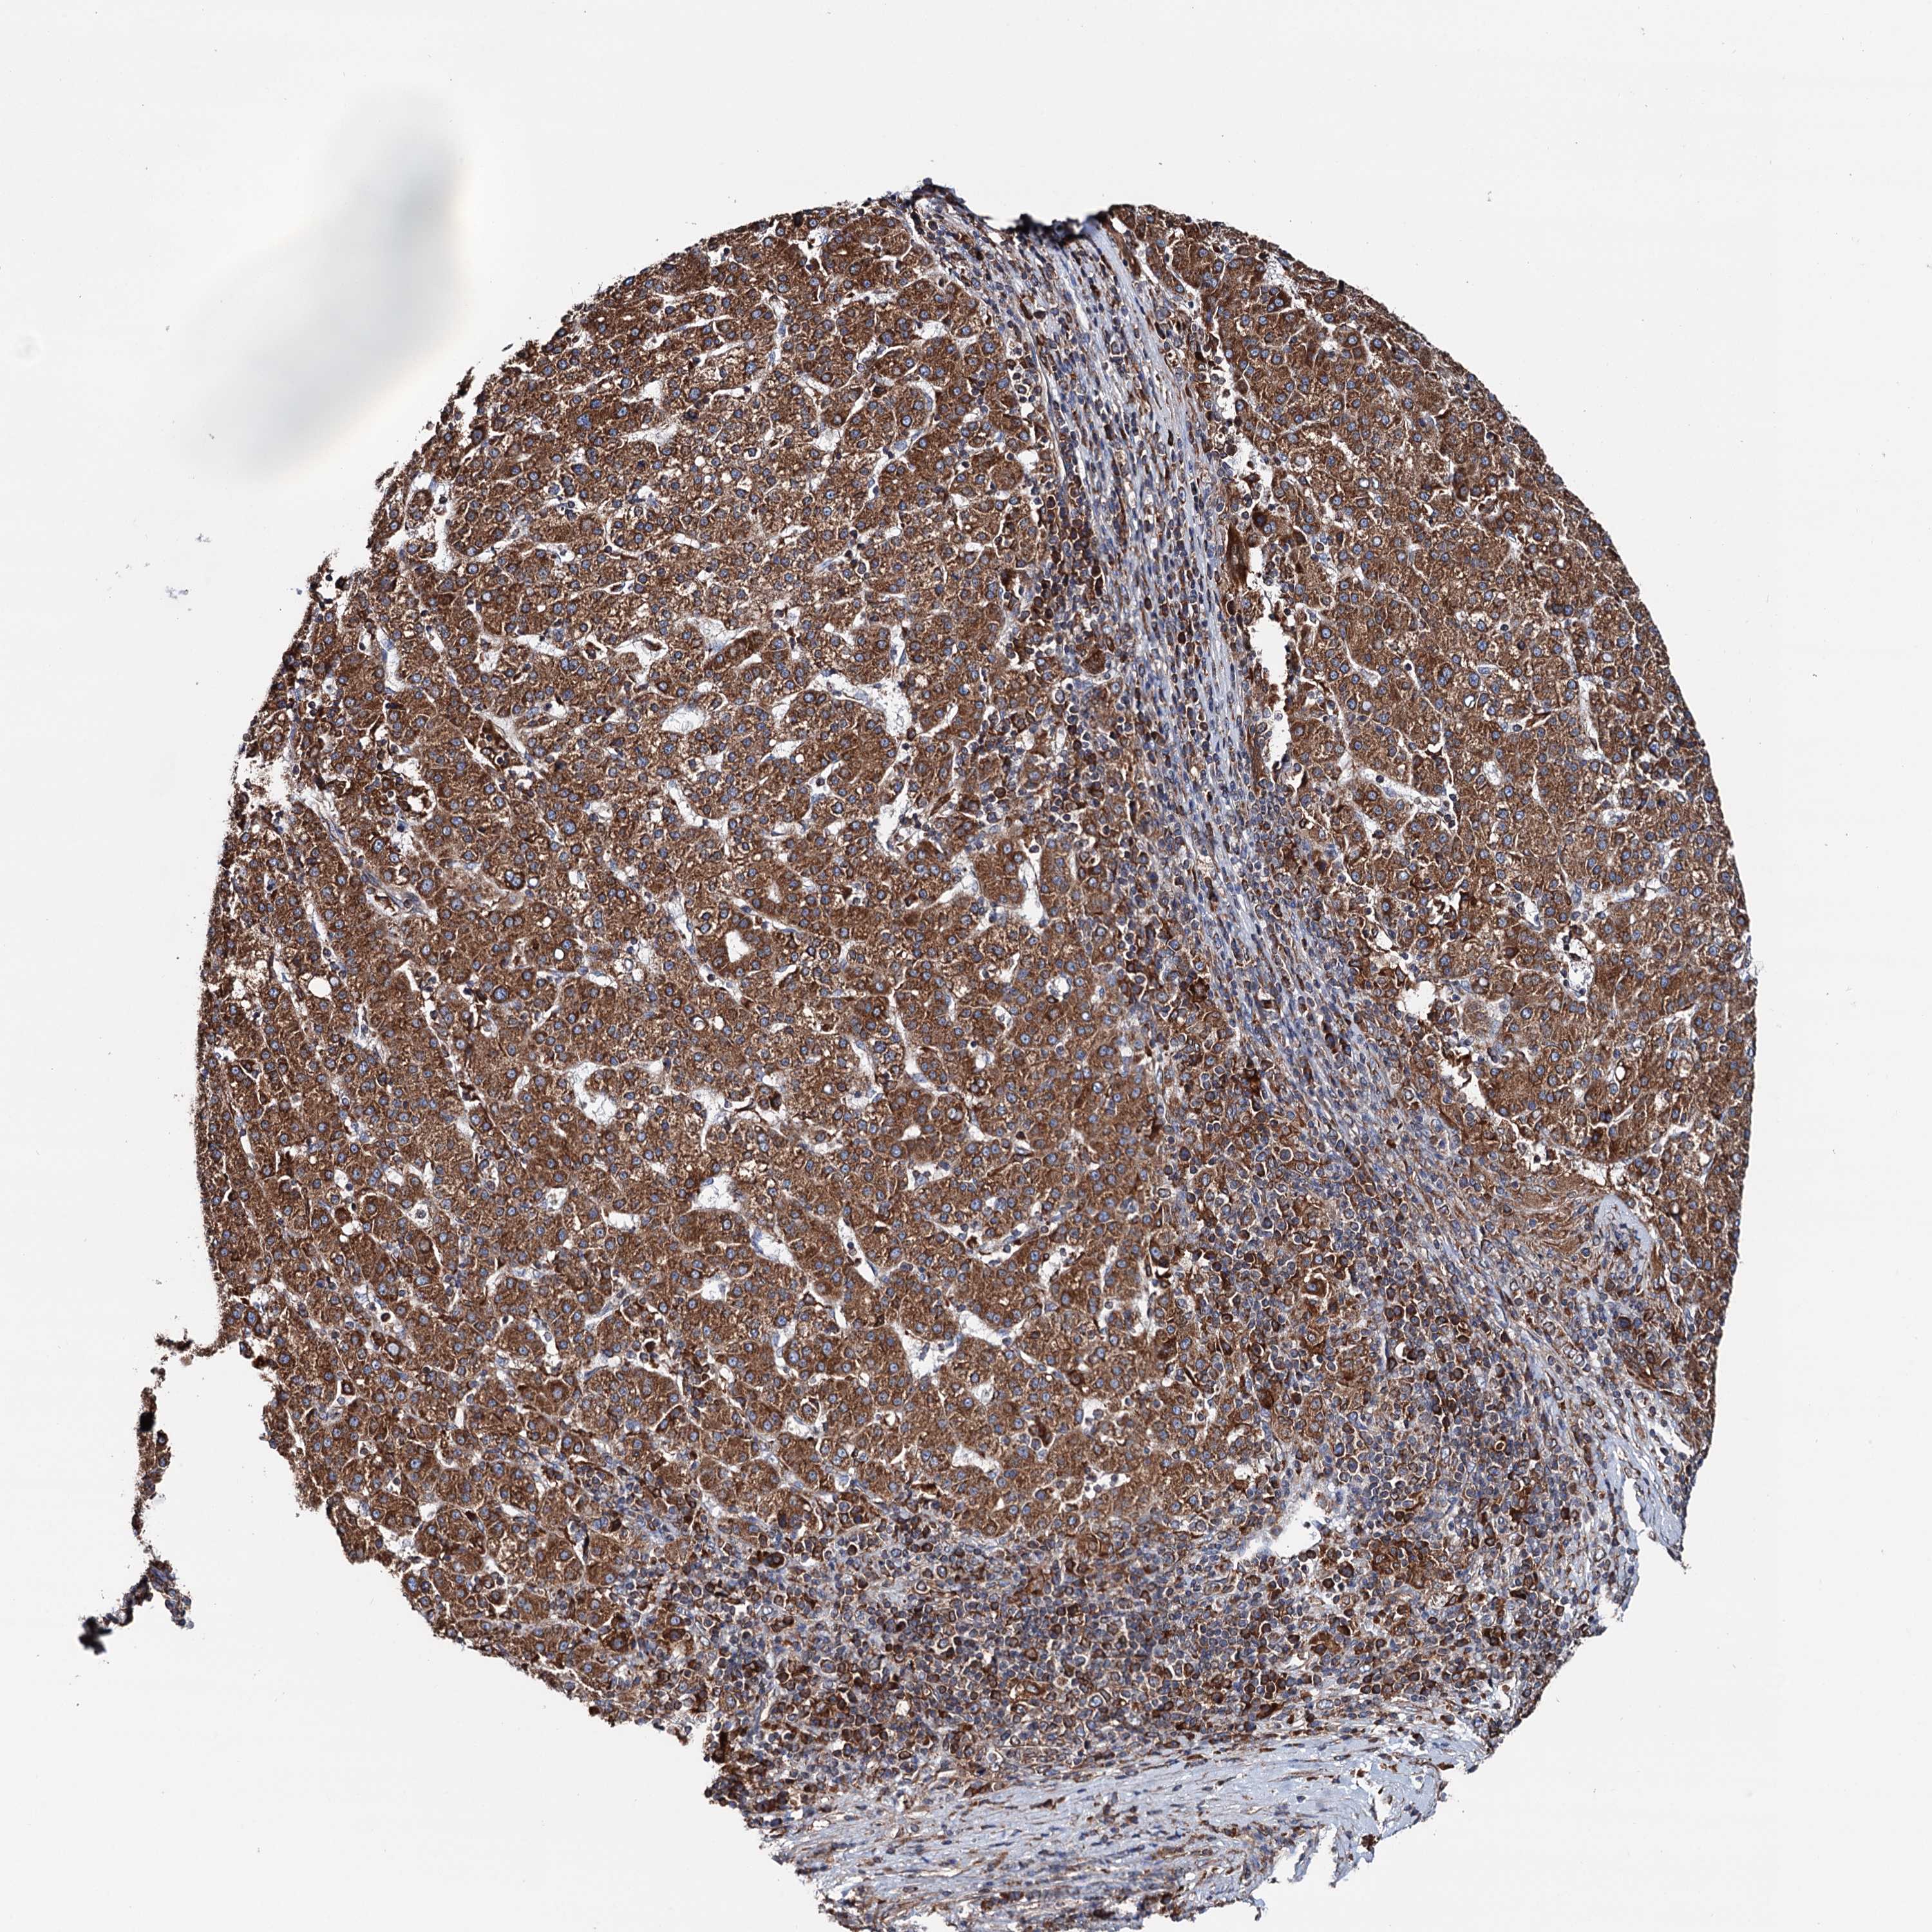

LIVER CANCER - Protein expressioni

A mouse-over function shows sample information and annotation data. Click on an image to view it in a full screen mode. Samples can be filtered based on level of antibody staining by selecting one or several of the following categories: high, medium, low and not detected. The assay and annotation is described here.

Note that samples used for immunohistochemistry by the Human Protein Atlas do not correspond to samples in the TCGA dataset.

Antibody stainingi

Antibody staining in the annotated cell types in the current human tissue is reported as not detected, low, medium, or high, based on conventional immunohistochemistry profiling in selected tissues. This score is based on the combination of the staining intensity and fraction of stained cells.

Each image is clickable and will lead to virtual microscopy that enables deeper exploration of all samples and also displays staining intensity scores, fraction scores and subcellular localization as well as patient and tissue information for each sample.

Antibody HPA039363

Antibody HPA039456

Staining

High

Medium

Low

Not detected

Intensity

Strong

Moderate

Weak

Negative

Quantity

>75%

75%-25%

<25%

None

Location

Nuclear

Cytoplasmic/membranous

Cytoplasmic/membranous,nuclear

Cholangiocarcinoma

Carcinoma, Hepatocellular, NOS